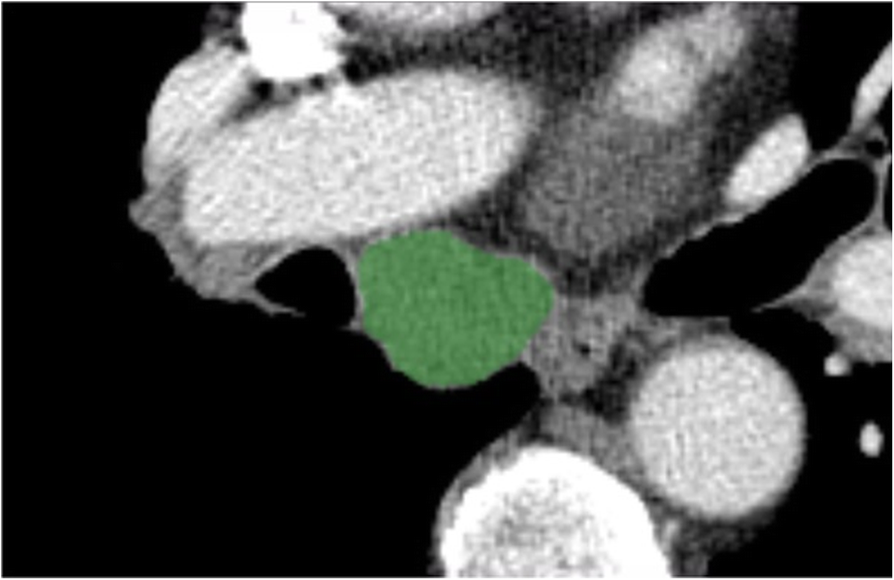

Fig. 2From: Quantitative computed tomography texture analysis: can it improve diagnostic accuracy to differentiate malignant lymph nodes?Representative computed tomography image illustrating a region of interest (ROI) demonstrating the enlarged subcarinal lymph node. The green highlighted area represents the ROIBack to article page